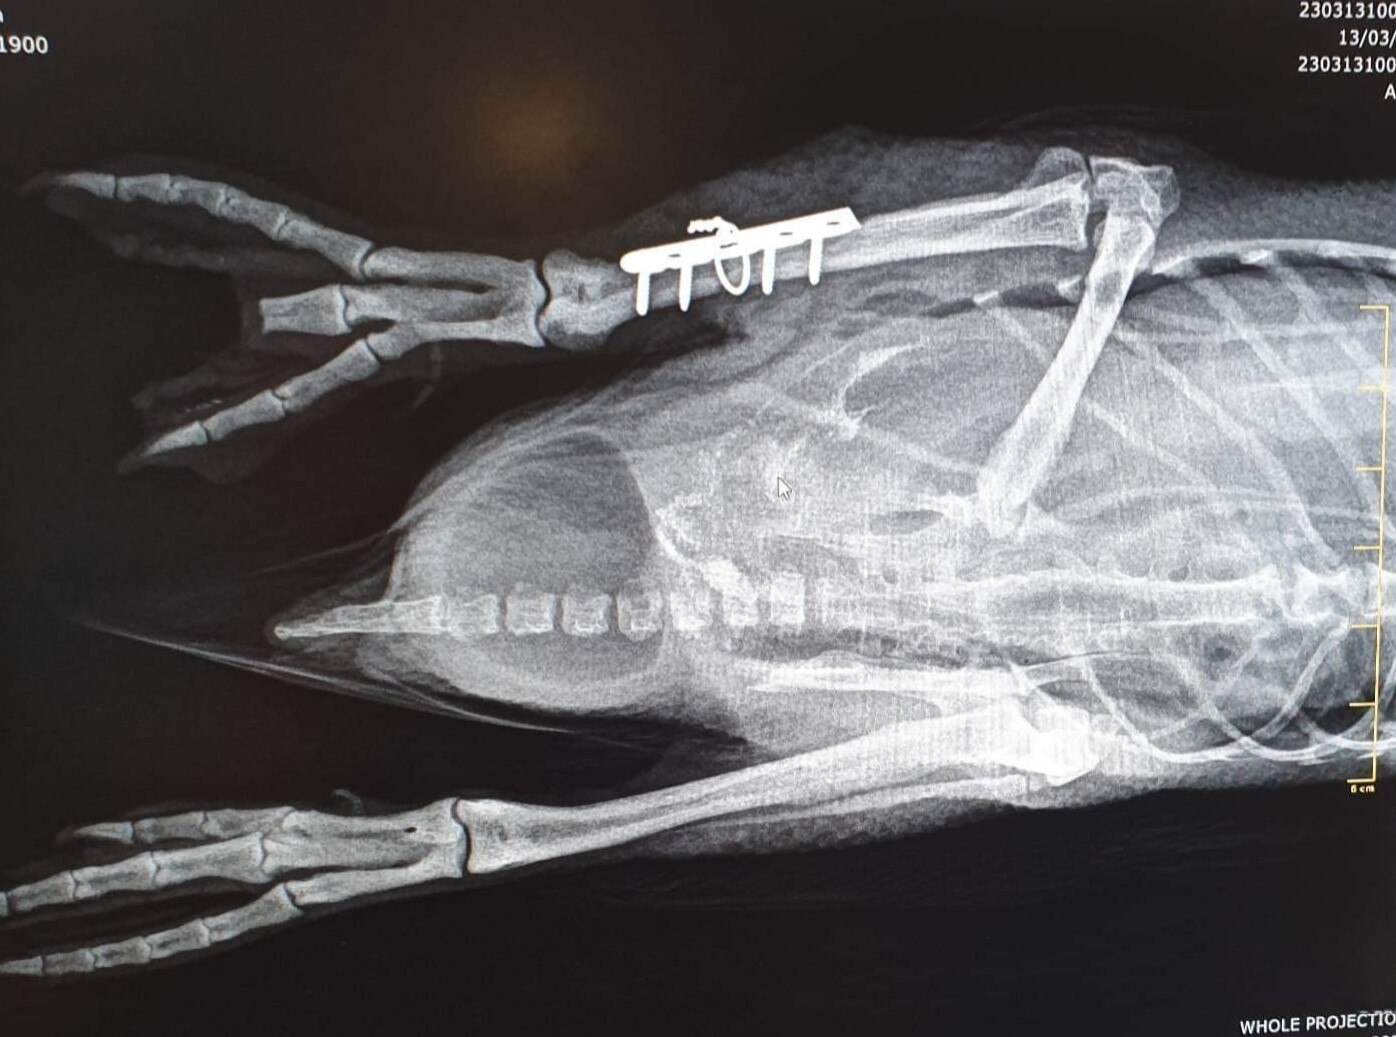

Senior veterinarian Jahk Hughes said the penguin presented with a fractured tibia, a broken toe "contaminated with sand and debris" and mild external wounds.

"The leg was completely broken in half," he said.

"It was in two pieces."

Dr Hughes said the Forth Valley Vet Clinic team inserted a plate into the penguin's leg which will likely remain in place.

But he said the toe was "damaged beyond repair" and they had to remove some of the webbing from the foot and remove part of his middle toe and resect the skin over it.